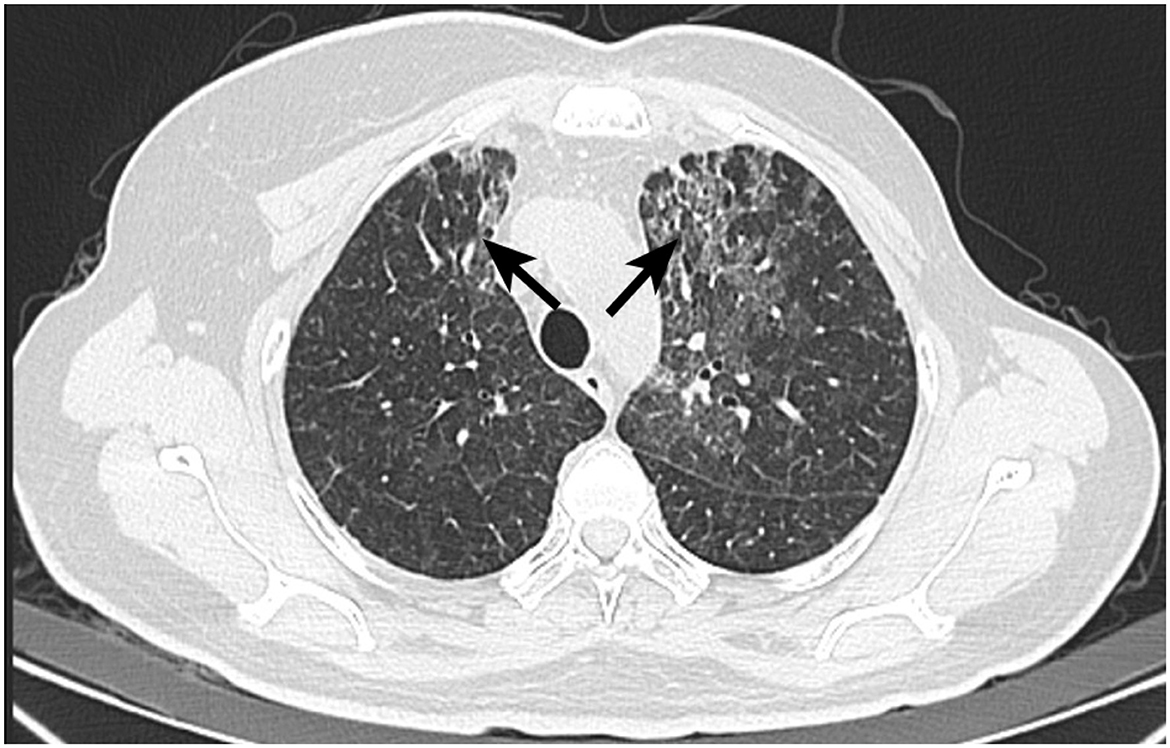

Five months post-radiotherapy, she developed worsening cough, dyspnea, and frothy white sputum, requiring ICU admission. CT indicated new diffuse ground-glass opacities and interlobular septal thickening, suggestive of ILD (Figure 3). She received symptomatic management (antitussives/anti-inflammatories). The patient received levofloxacin 0.5 g QD (6 days), meropenem 0.5 g Q8H (8 days), and compound sulfamethoxazole tablets 0.96 g BID (9 days) for anti-infection treatment. Moreover, methylprednisolone (40 mg/d) was administered intravenously for 3 days, followed by oral prednisone (40 mg/d) for 1 month. Then, the patient had initiated goserelin + fulvestrant + dalpiciclib treatment, which she continues at present. Figure 4 showed the timeline of diagnosis, interventions and outcomes for two patients.

Figure 3. CT image of Patient 2 with interstitial lung disease. Postoperative changes after left breast cancer surgery, with streak and multiple high-density foci in the surgical area, generally unchanged in extent. Multiple faint small nodules and patchy opacities in both lungs, significantly increased from prior, metastasis cannot be excluded. Short-term follow-up after anti-inflammatory treatment is recommended. Possible interstitial lung disease is at the left lung apex. Scattered inflammatory organized foci in the right lung with corresponding pleural thickening, showing little change from previous.